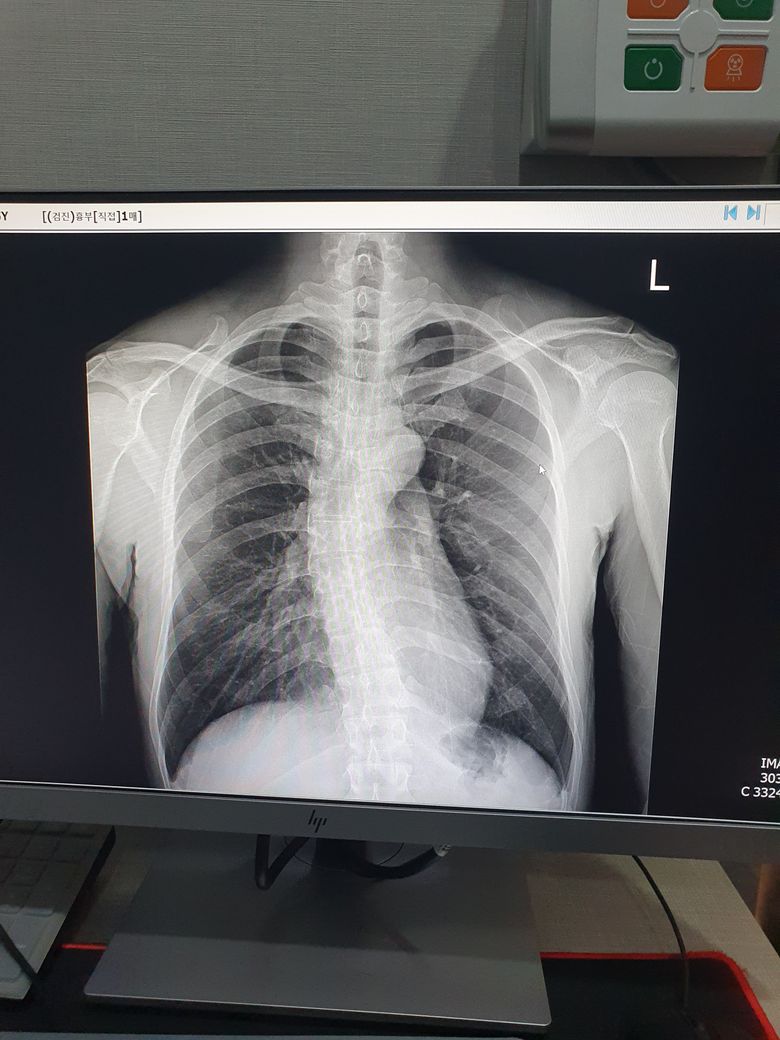

선생님 폐 엑스레이 사진좀 봐주세요.

직장검진에서 폐사진을 찍었는데 우측 폐 결절이 보인다고 혹시 모르니 큰병원에 가보라고 하십니다.

• 엑스레이로는 우측 결절이 명확하게 보이지는 않는데 척추측만증이 있어서

우측 폐가 밀리면 결절처럼 보이는 경우도 있습니다. 그래도 검진으로 시행한

병원에서는 영상 의학과 판독일 가능성이 높아서 CT 를 찍어 보는 것이

안전할 수 있습니다.

• 엑스레이상으로는 폐결절 자체에 대한 평가가 어렵지만 엑스레이상 크지 않아 우선 크게 우려하지 않으셔도 될것으로 사료되며 권유받으신대로 추가검사를 하시면 되겠습니다.